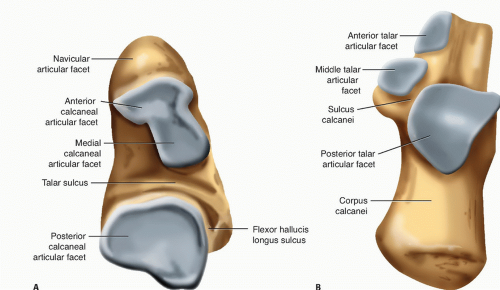

what is the talus composed of?

head

neck

body

what is the calcaneus?

longest and strongest tarsal bone

what is an important landmark of the calcaneus?

sustentaculum tali

what is the sustentaculum tali?

shelf of calcaneus where tali sits on

what is the subtalar joint?

below talis

what are the 3 articulations of the subtalar joint?

anterior

middle

posterior